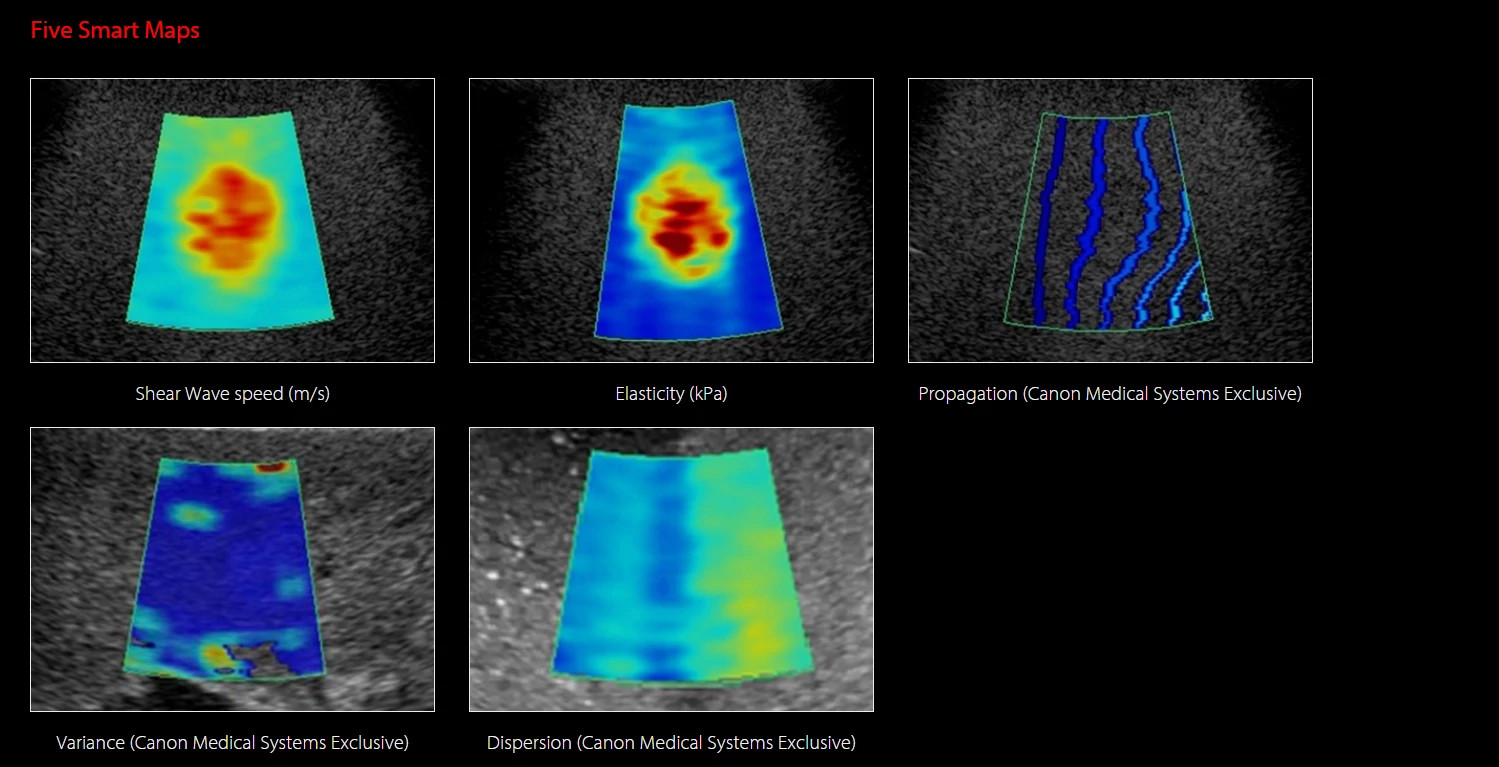

Aplio i-Series Liver Analysis Package - A májbetegségek teljes spektrumának lefedése

A májbetegségek diagnosztikája napjaink egyik legnagyobb képalkotó kihívása.

A diagnosztikus bizonyosság érdekében a Canon új és egyedi képalkotó technológiákat fejlesztett,

melyek a májállapot változásainak vizuális és kvantitatív megjelenítését teszik lehetővé.

A Canon Shear Wave technológiája kvantitatív és dinamikus vizuális információt nyújt a szöveti merevségről különböző klinikai környezetekben.

Multi-Parametric Report - Integrált jelentés májalkalmazásokhoz

A multiparametrikus jelentés képes egyesíteni az ultrahangos és külső vizsgálatok (pl. laboreredmények) adatait, hogy átfogóbb képet adjon a máj állapotáról.

Az eredmények táblázatos formában vagy pókháló (spider) diagramon is megjeleníthetők, ahol a vizuális mintázat segíti az eredmények közötti összefüggések értelmezését.

A jelentés kombinálható a következő modulok eredményeivel:

Shear Wave Elastography

Shear Wave Dispersion Map

Attenuation Imaging